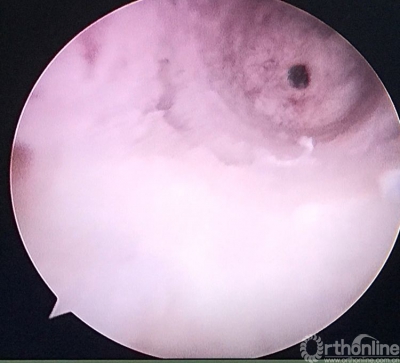

股骨隧道内取出的原重建肌腱及袢,糜烂。

己经完成的股骨隧道,改用强生横穿钉固定。